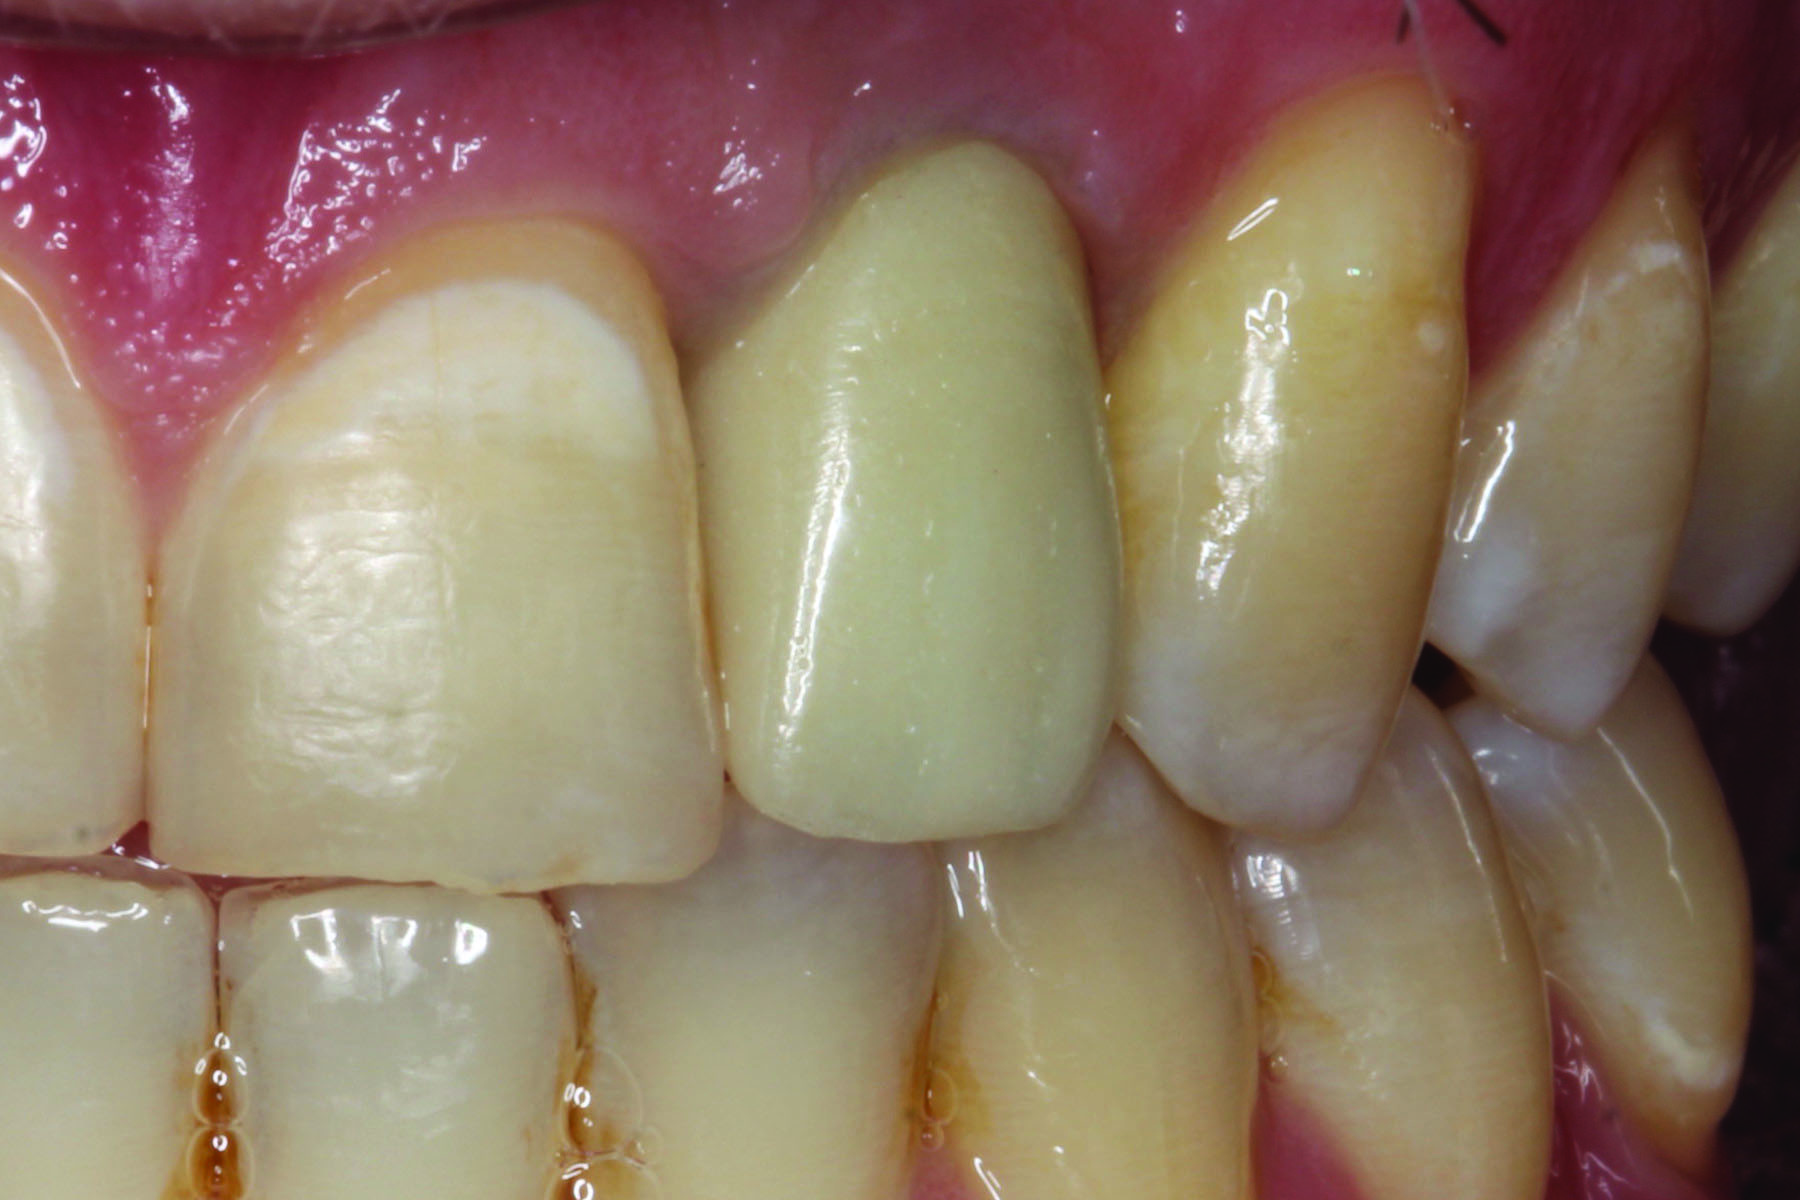

Fig 4. Lithium-disilicate crown cemented over the gold anodized titanium custom abutment shown in Fig 3.

Figure 4

Fig 3. Gold anodized titanium custom abutment in preparation for crown cementation.

Figure 3

Figure 3 and Figure 4 show a gold anodized abutment and an overlying lithium-disilicate restoration, respectively. Zirconia is a relatively opaque ceramic, and studies are less clear as to the benefit of the use of gold anodized abutments under zirconia implant crowns. One study of 0.7 mm to 1.1 mm thick zirconia specimens reported that gold anodization of a titanium background did not improve the color match to a zirconia crown against a zirconia background.10 On the other hand, another study reported that the color change of 0.5 mm thick zirconia specimens against titanium backgrounds could be improved by gold anodization.11